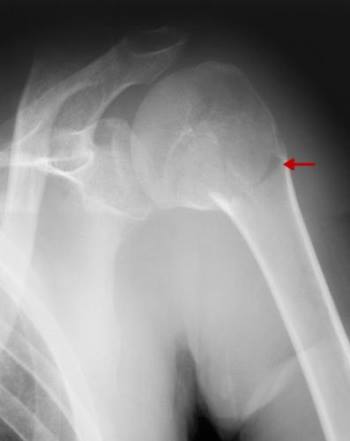

НА ЯКИЙ СУГЛОБ ВКАЗУЄ СТРІЛКА НА РЕНТГЕНОГРАМІ? КІСТКИ ЯКОГО ВІДДІЛУ СКЕЛЕТУ ВІН З'ЄДНУЄ?

варіанти відповідей

ГРУДНИННО-КЛЮЧИЧНИЙ С.

ПЛЕЧОВИЙ С.

НАДПЛЕЧОВО-КЛЮЧИЧНИЙ С.

АКРОМІАЛЬНО-КЛЮЧИЧНИЙ С.

КІСТКИ ВЕРХНЬОЇ КІНЦІВКИ

КІСТКИ ТУЛУБА І ВЕРХНЬОЇ КІНЦІВКИ